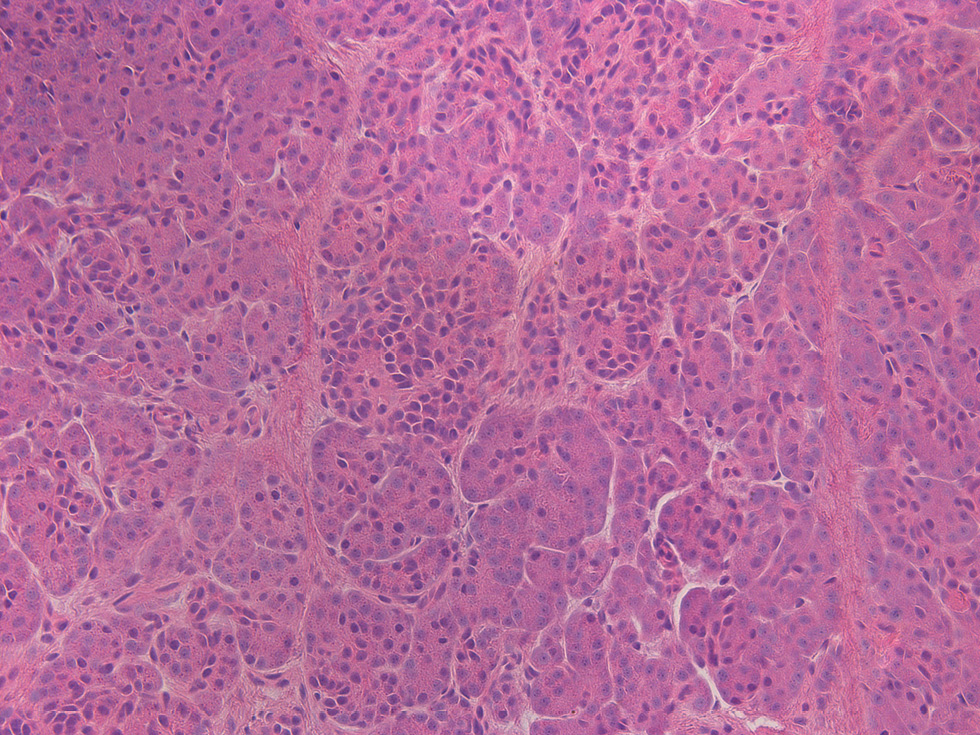

Несмотря на относительную эугликемию у части больных на фоне лечения октреотидом или диетотерапии, всем пациентам было проведено хирургическое вмешательство. Показания к оперативному лечению были обусловлены высоким риском развития гипогликемии на фоне пропуска приема пищи, тахифилаксией при применении октреотида, а также возможностью полного излечения после проведения резекции фокуса [23]. Большей части (25/31) детей выполнена резекция участка аденоматоза с проведением интраоперационной гистологической диагностики для оценки края иссечения (рис. 4). Проведение субтотальной панкреатэктомии пациентам с фокальной формой ВГИ было связано с отсутствием возможности проведения полной предоперационной диагностики, в частности ПЭТ/КТ с 18F-ДОФА на момент обследования.

Рис. 4. Гистологическое исследование ткани поджелудочной железы у пациента с фокальной формой ВГИ.

а – фокус гиперсекреции инсулина, метаплазия островков (окраска гематоксилином и эозином, ×20); б – выраженная экспрессия инсулина в фокусе при проведении иммунногистохимии; в – ткань поджелудочной железы вне фокуса гиперсекреции инсулина (окраска гематоксилином и эозином, ×200); г – низкая экспрессия инсулина вне фокуса при проведении иммунногистохимии.